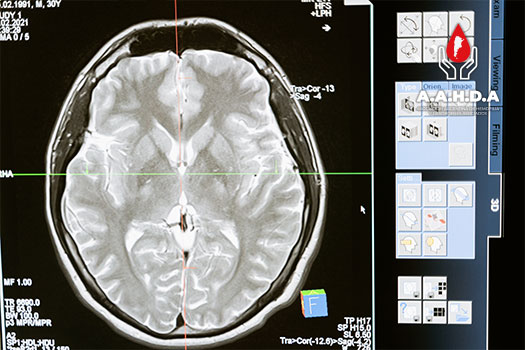

PROTOCOLOS IMÁGEN: RMI

DENVER

International Prophylaxis Study Group